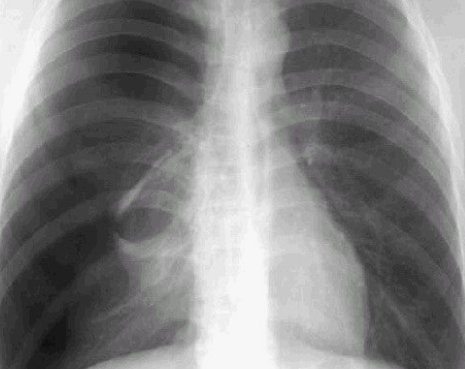

폐기흉은 폐에 구멍이 생겨 공기가 흉막강으로 유입되면서 폐가 정상적으로 기능하지 못하는 질환입니다. 초기에는 단순 통증으로 보일 수 있지만, 심각해지면 호흡부전으로 이어질 수 있어 조기 진단과 치료가 중요합니다.

폐기흉은 크게 자발성, 이차성, 외상성으로 구분됩니다. 특히 키가 크고 마른 체형의 젊은 남성, 흡연자에서 발생 위험이 높습니다. 자발성은 별다른 질환이 없는 상태에서 갑자기 나타나며, 이차성은 결핵이나 폐기종, 폐암 같은 기저 질환이 원인이 됩니다. 외상성은 교통사고, 수술, 시술 중 손상으로 발생합니다. 생활 습관과 기존 질환이 주요한 원인 요인으로 작용합니다.

폐기흉의 증상은 갑작스럽게 나타나며 빠른 대처가 필요합니다. 대표적으로 갑작스러운 흉통과 호흡곤란이 있으며, 심할 경우 청색증, 호흡부전, 심장 기능 저하까지 이어질 수 있습니다. 폐기흉 환자의 약 절반은 재발할 수 있어, 초기 증상 발생 시 지체 없이 의료진의 진단을 받는 것이 중요합니다. 경미한 증상이라도 무시하지 않고 빠른 대응이 필요합니다.